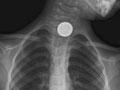

Your doctor may recommend tests such as an X-ray, endoscopy, or barium swallow. These tests can help find the object if it doesn't come out in the stool or if an inhaled object isn't coughed out. A special metal detector might be used. It can help locate a metal object, such as a coin, inside the body. Your doctor may then recommend a procedure to remove the object. Or your doctor may encourage you to keep checking the stool to be sure the object passes out of the body.

Have you swallowed a coin?

Did you swallow the coin more than 24 hours ago?

Most coins pass through the body without a problem in 24 hours. If you don't pass the coin in this time frame, it's best to follow up with your doctor.